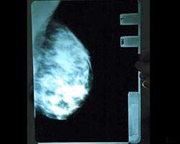

Джорджина Вербаан разместила копию маммографии на своем веб-сайте, чтобы, наконец, развенчать слухи о силиконовом наполнении своего пышного бюста. Грудь 25-летней актрисы в последнее время стала излюбленным предметом обсуждения для голландской желтой прессы. В этом месяце Вербаан появилась на страницах местного издания журнала «Плейбой». Но изображения актрисы в костюме Евы лишь подлили масла в огонь, и в богемных кругах еще громче заговорили о неестественном происхождении ее прелестей.

Но после того как Вербаан выложила в Интернете снимки с целью доказать натуральность своей красоты, организация NVMBR заявила, что использование рентгеновской технологии с целями, отличными от медицинских, является незаконным. По словам президента ассоциации Фреда Фелдерхофа, голландские законы регламентируют использование рентгена. Чтобы доказать натуральность груди, Вермаан могла бы прибегнуть к менее экстремальным методам, например, ультразвуку, добавил Фелдерхоф.